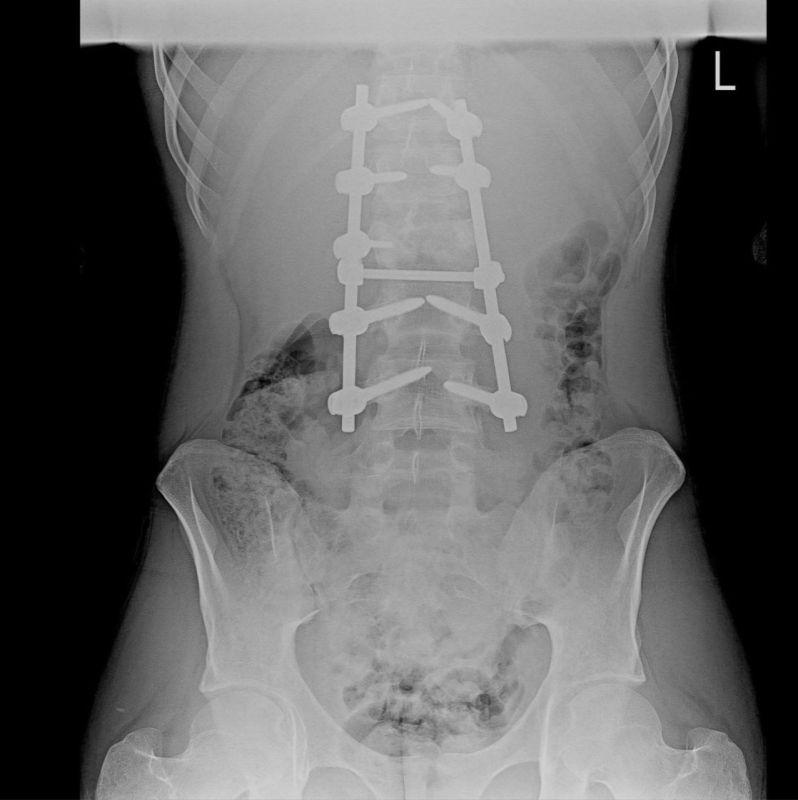

Воронежские медики провели подростку сложнейшую операцию на позвоночнике

В областной клинической больнице парню провели сложнейшую операцию. Хирурги сделали всё, чтобы сохранить нервные структуры и дать шанс на восстановление.